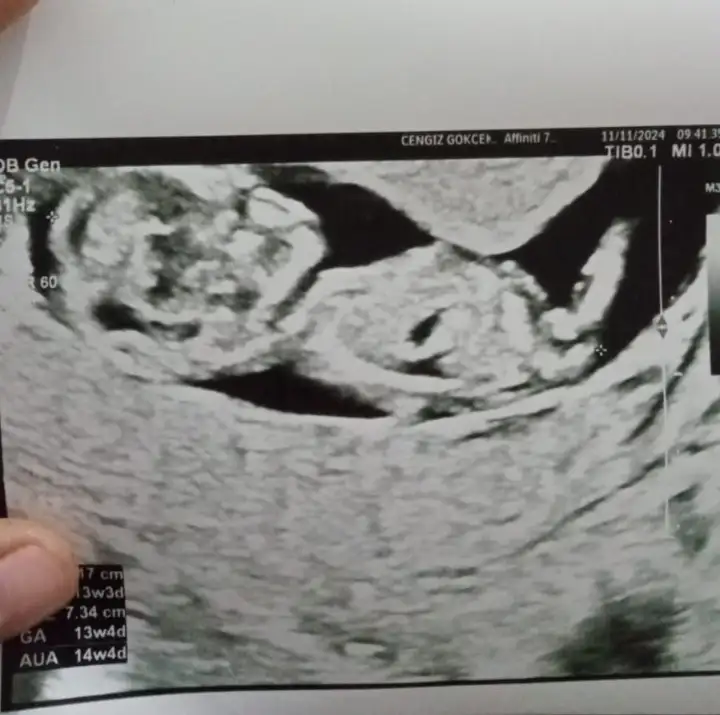

Bejimkide bakarmisiniz 13 haftalıkSizinki kiz

Banada bakarmisiniz 13 haftalıkBence net kız![]()

Banada bakabilirmisiniz 13 haftalıkKesinlikle kızzzz nub'u eğik